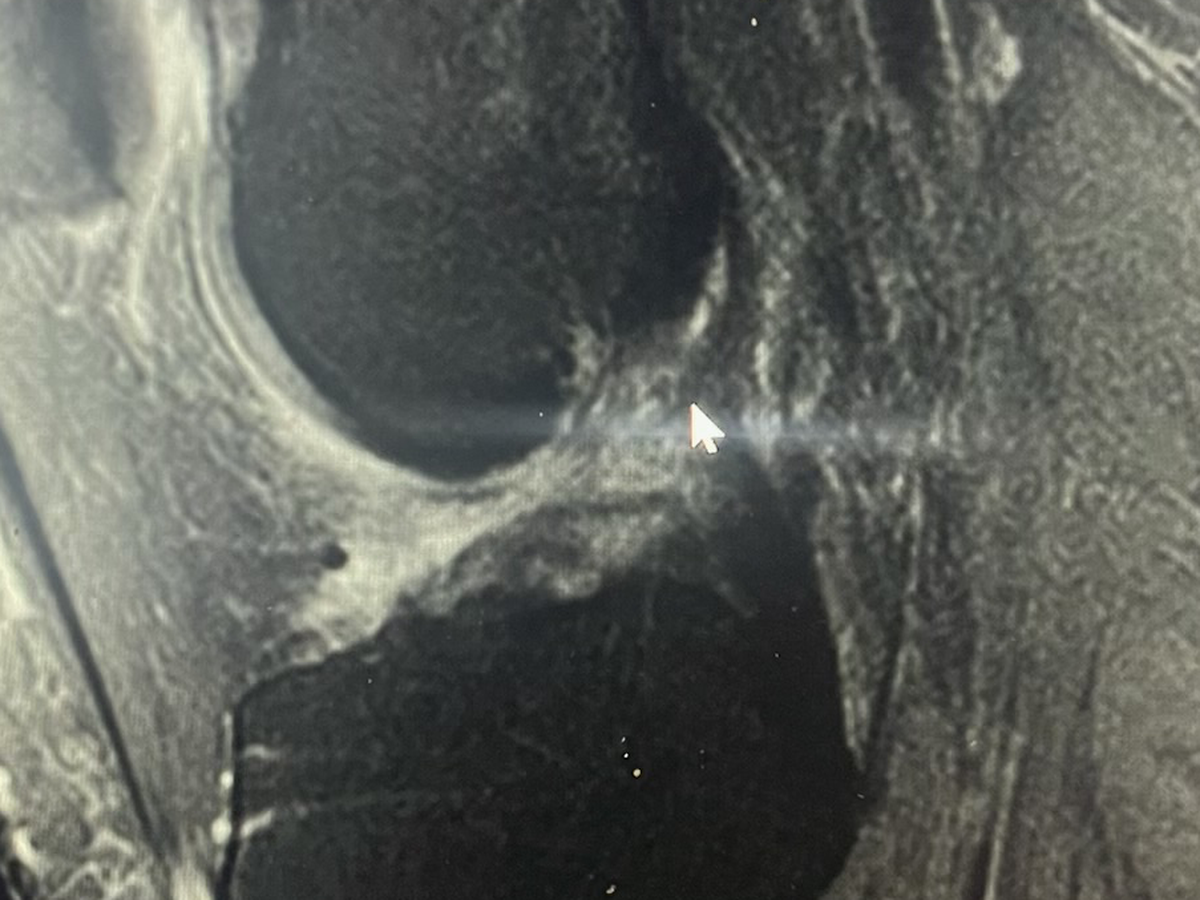

Some of you may know, but I took a fairly bad fall at work while in the kitchen and damaged my knee significantly enough to require surgery. Any money that is donated will be going towards medical costs that insurance won’t cover. On the 1st of July, I'm having an Arthroscopic Assisted ACL Reconstruction With Quadriceps Tendon Autograft, Medial And Lateral Meniscus Repair, and Osteochondral Lesion Repair With Cartiheal Agili-C Implant.

I’m looking at 3 weeks of bed rest, 6-8 weeks before I can walk again without crutches, and 10 months before I’ll be walking like normal. Please keep me in your prayers as I go through the lengthy recovery process!

The attached photo is an MRI of my knee showing my ACL (or lack thereof lol)